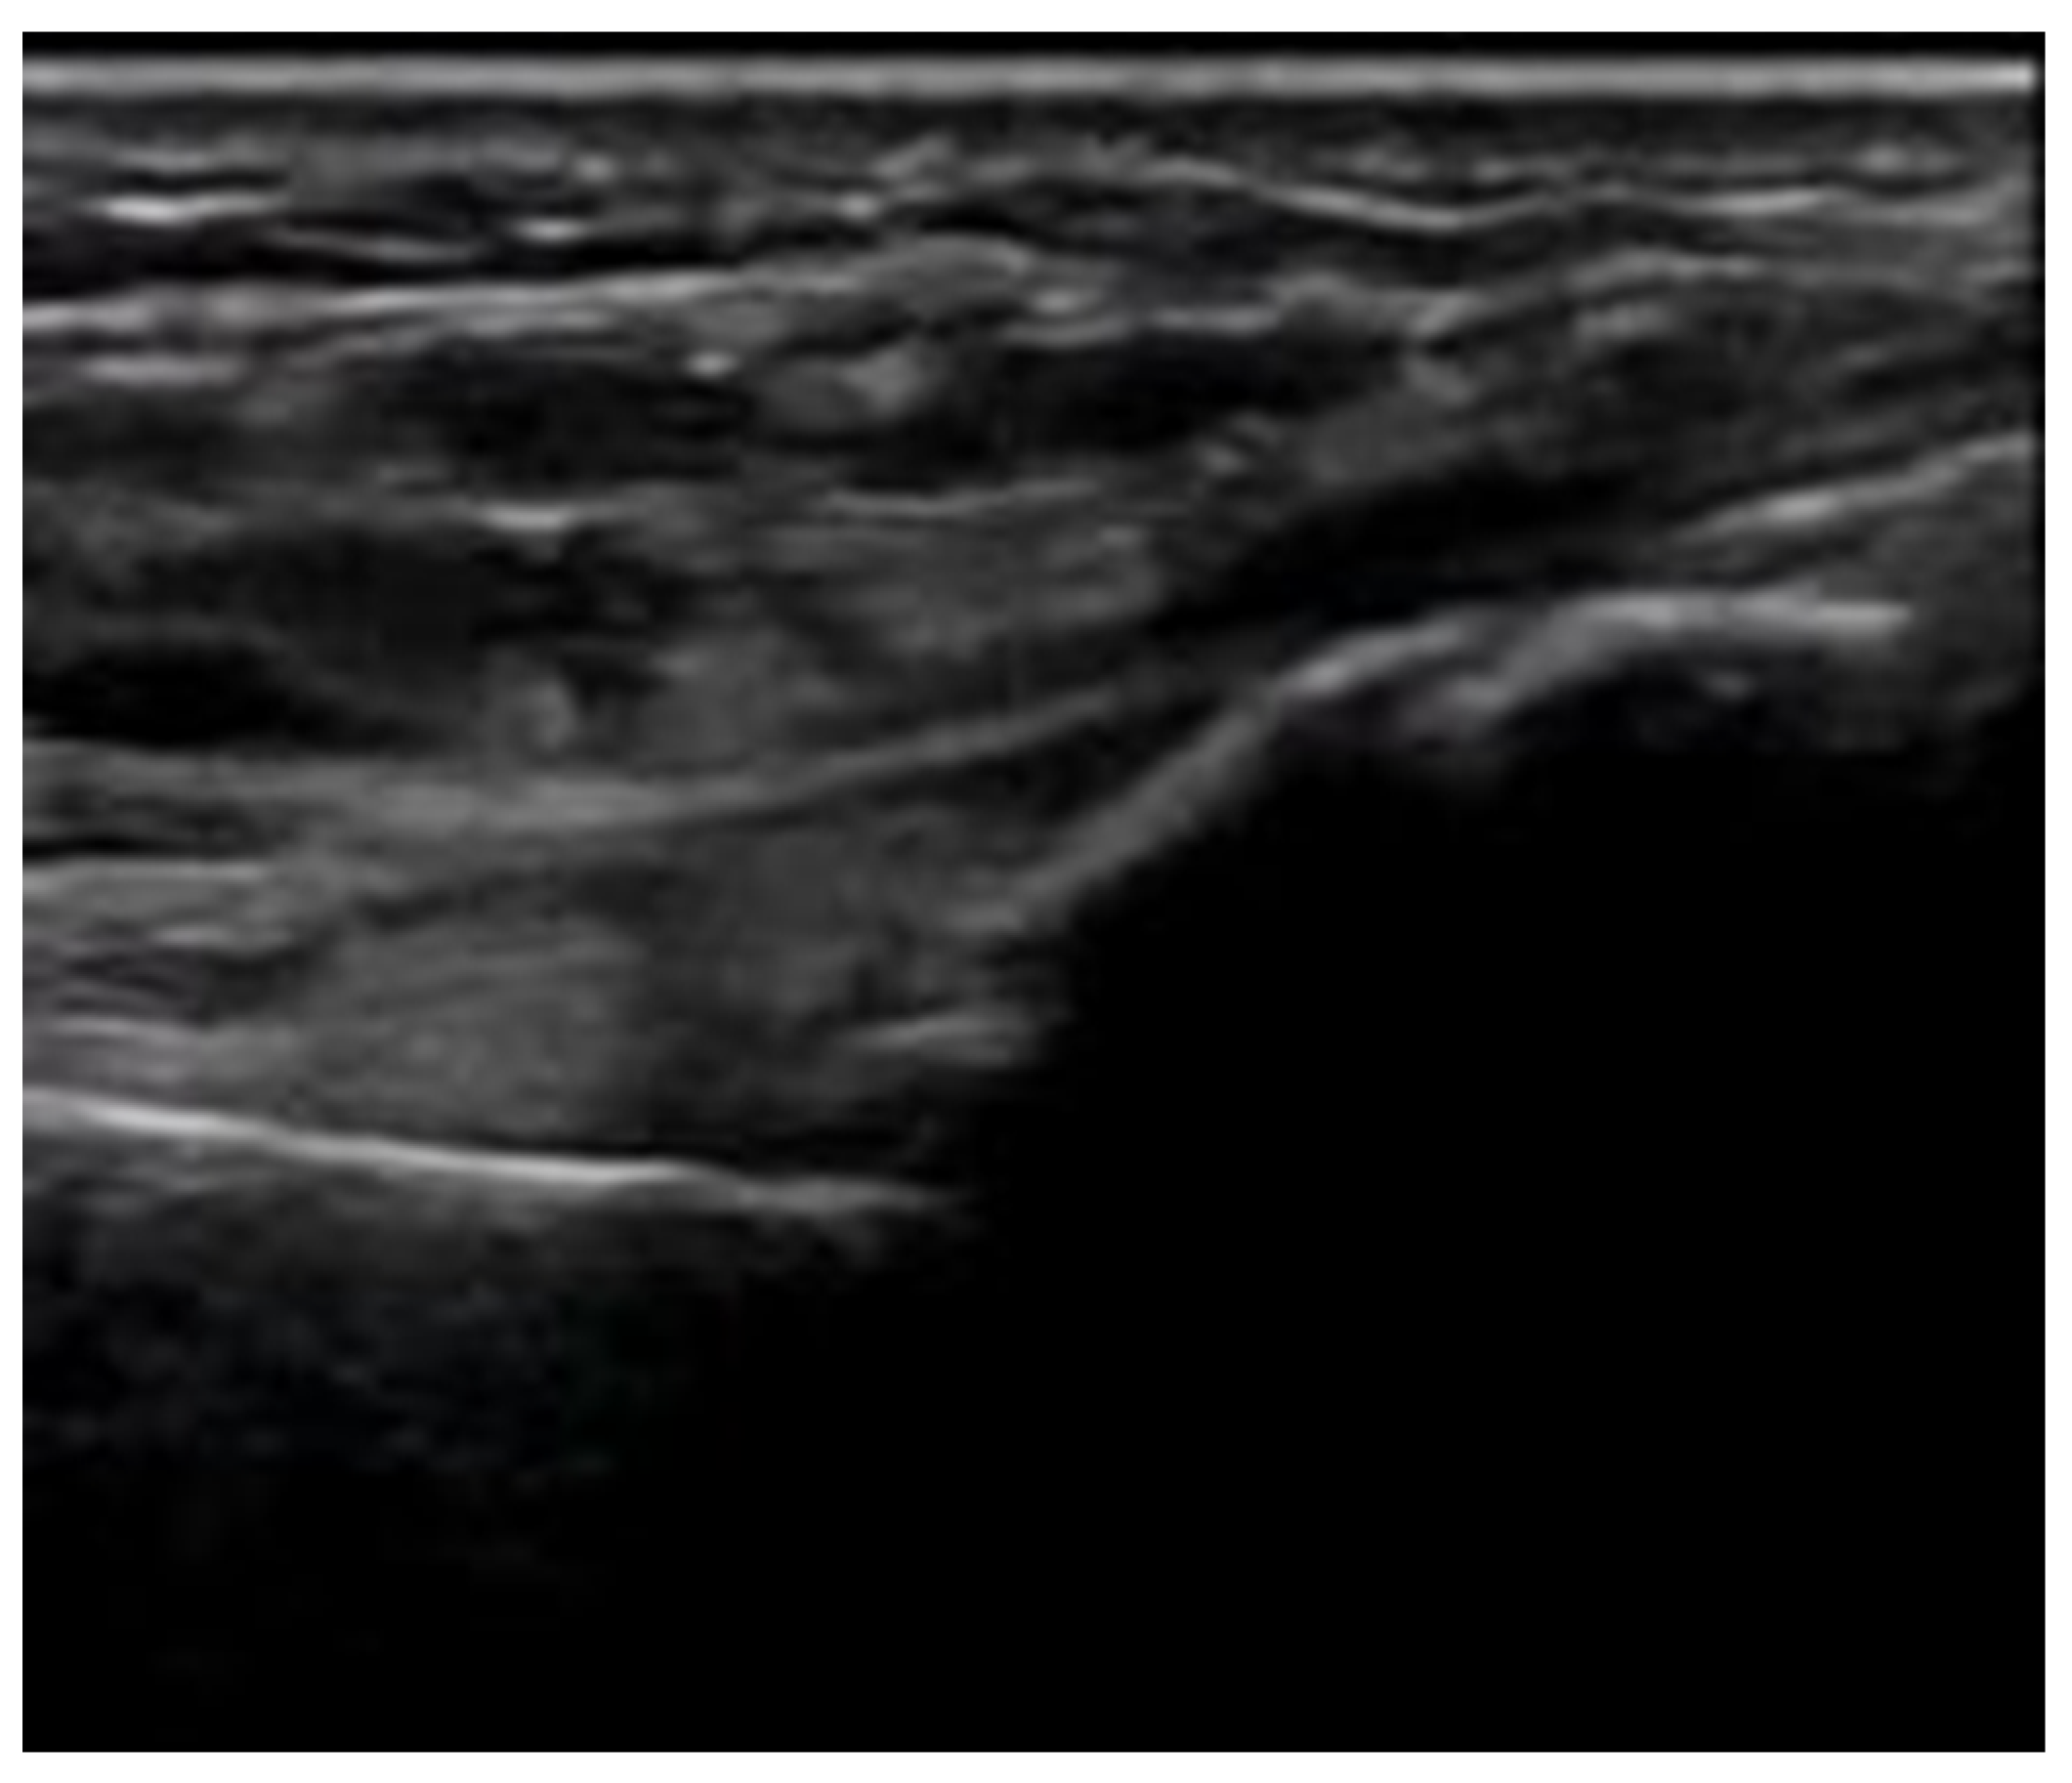

4.2. Sonoanatomy of Fractures [Figure 5, Figure 6, Figure 7 and Figure 8]

- Irregularity, interruption, or gaps in the cortical line: the cortical bone normally appears as a continuous, bright echogenic line, which is interrupted or irregular in the presence of a fracture.

- Bulging or abnormal angulation of the cortical layer: deformities or outpouchings of the normally straight cortical surface indicate displacement or bending at the fracture site.

- Local hematoma or soft tissue edema: fluid collections or increased echogenicity near the fracture site indicating bleeding and inflammation.